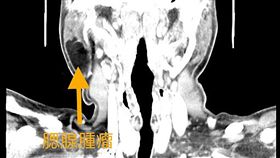

耳下腫脹誤認豬頭皮 後得知腫瘤上身

33歲王姓男子覺得左側耳下有點腫脹,以為是俗稱的「豬...

2019/11/07 15:56